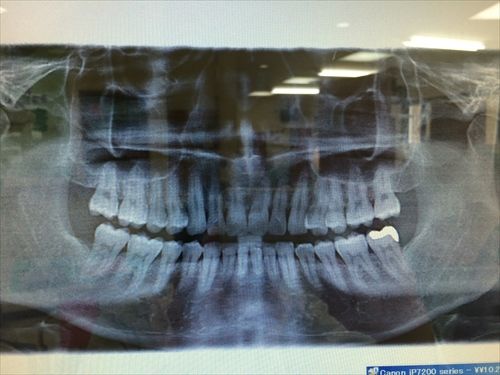

レントゲンに~軽い歯石とりに~ 歯医者さんの言われるままにしてしまったよw

レントゲンなんか10ヶ月前に撮ったばかりなのに・・

結果、「軽い歯周病以外何も異常ありません、このまま維持してください」だって・・